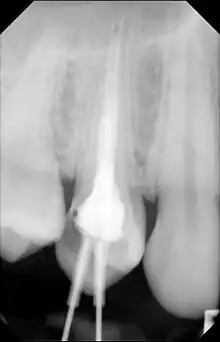

| Cone beam CT scan presenting a diffuse hyperdense lesion in the apex of a mandibular molar (arrowhead, top) adjacent to an inflammatory periapical lesion (arrow, bottom).[1] | |

Diagnosis typically involves a clinical examination by a dentist or endodontist, complemented by imaging studies such as cone-beam computed tomography. Radiographically, condensing osteitis presents as a localized radiopaque lesion at the root apex of the affected tooth.[7]